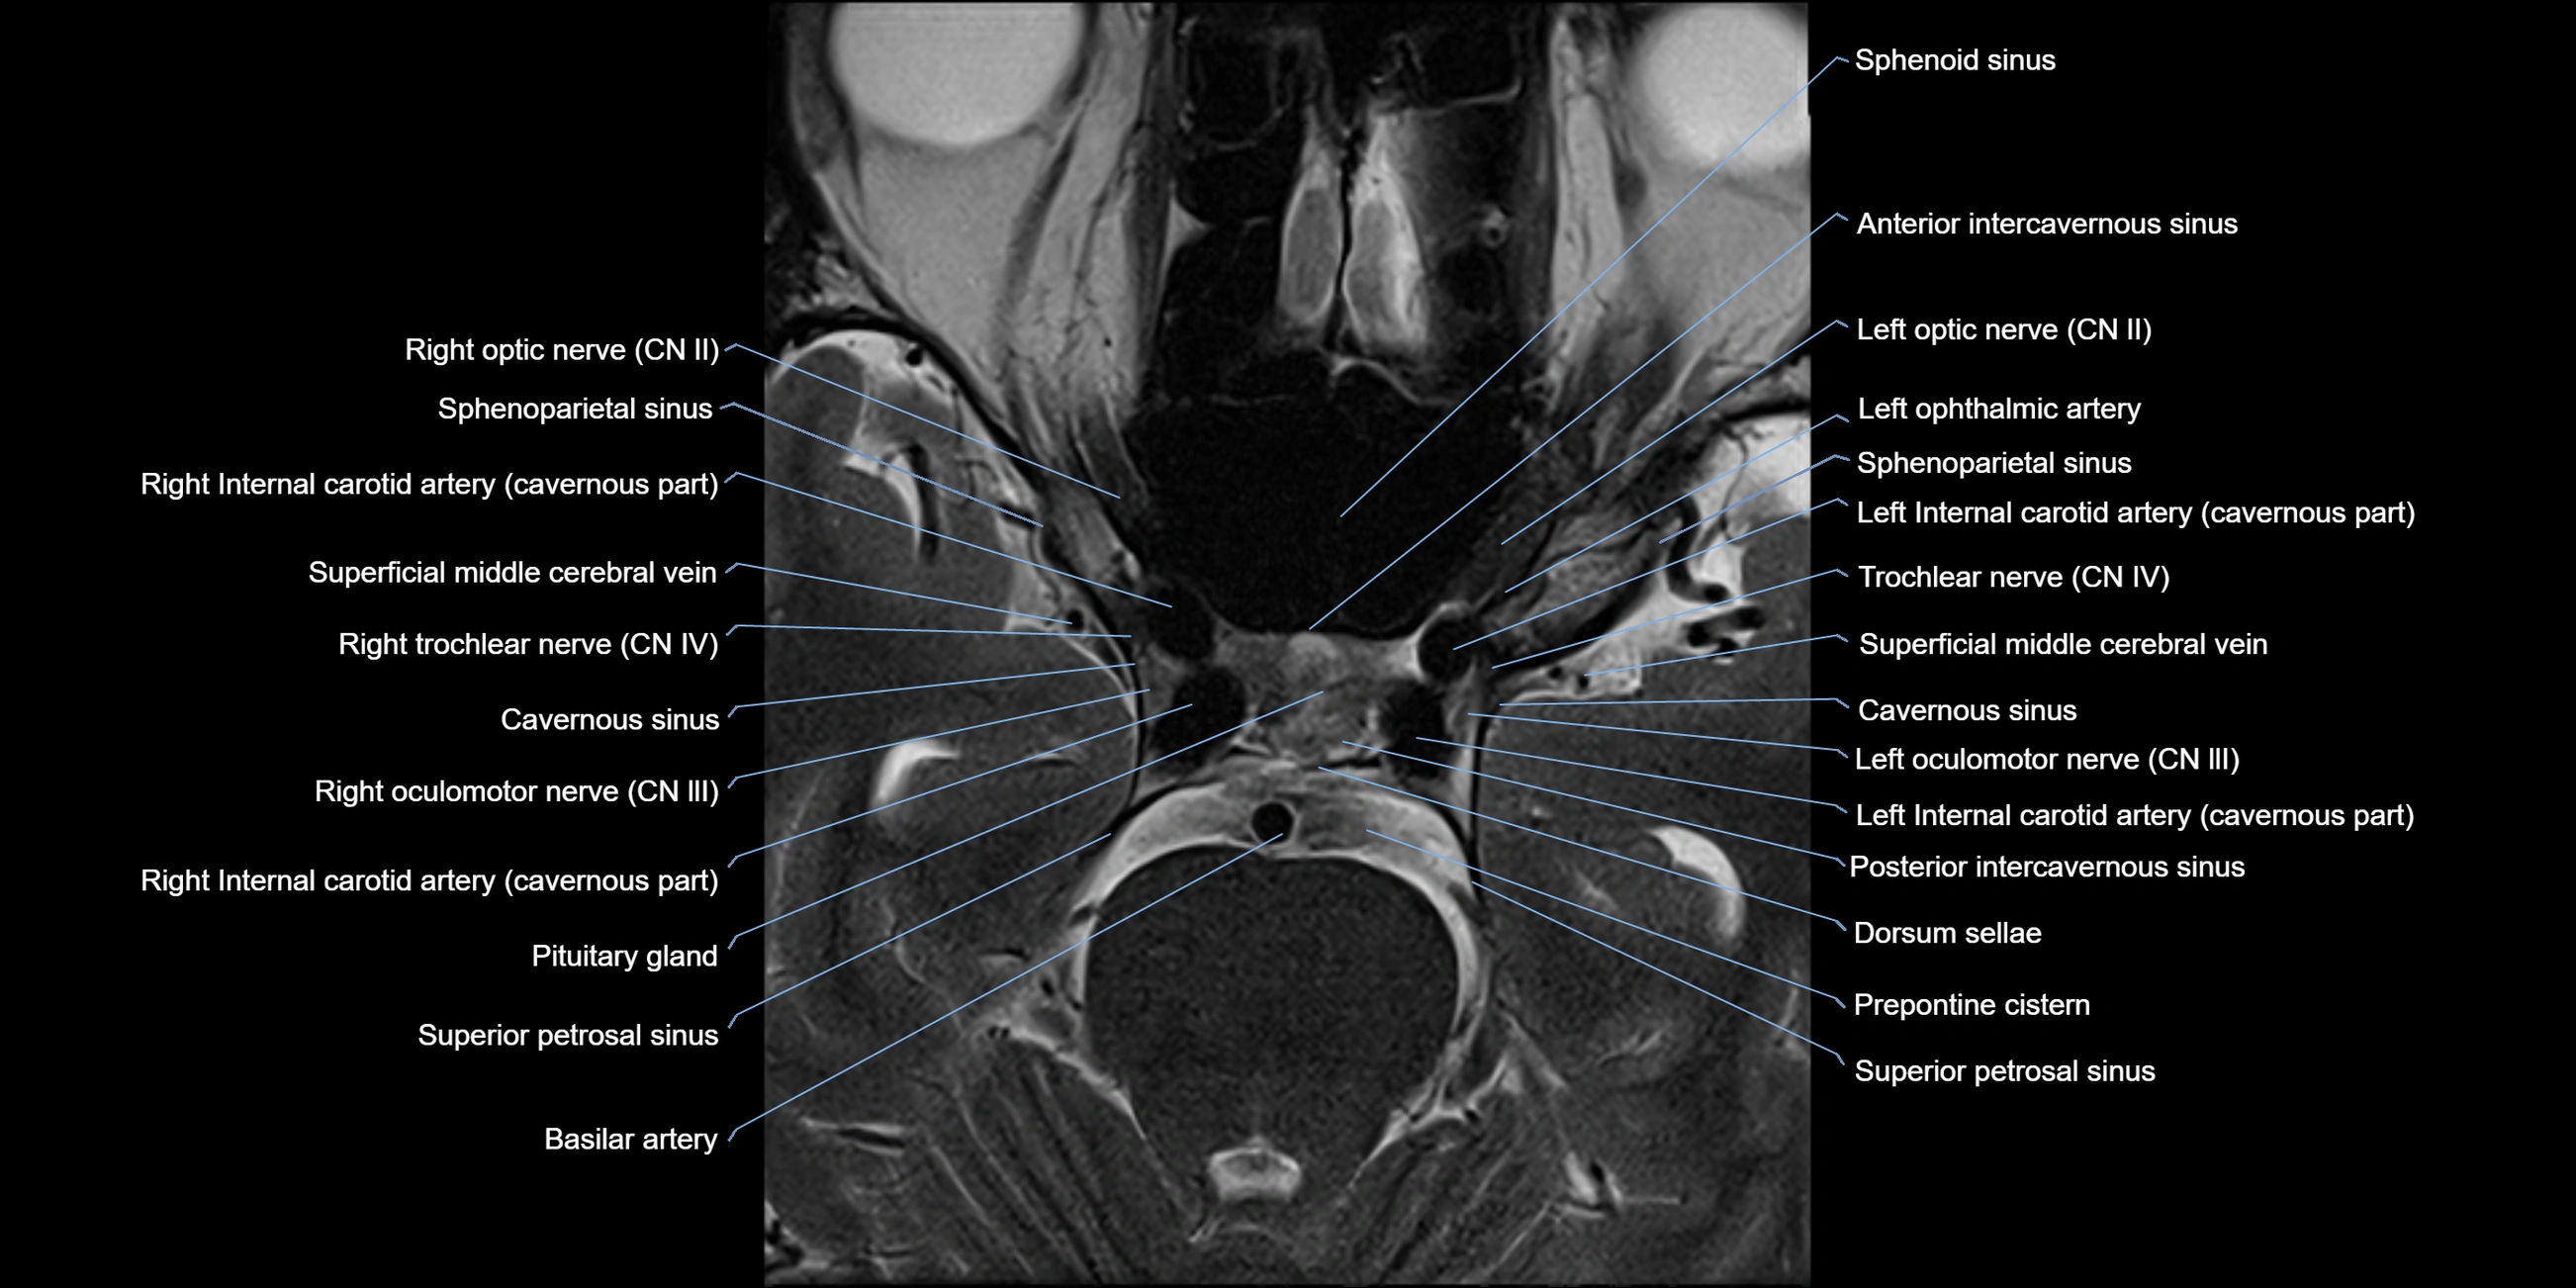

MRI Appearance

The abducens nerve is a small, thin, linear structure

Best visualized on high-resolution T2-weighted 3D MRI sequences (e.g., FIESTA or CISS)

Seen as a hypointense (dark) line running from the brainstem at the pontomedullary junction, traversing the prepontine cistern, and entering Dorello’s canal under the petrosphenoidal ligament, then into the cavernous sinus, and finally the orbit

May be challenging to visualize in standard MRI due to its small size

Pathology may be inferred by absence, displacement, or enhancement of the nerve

MRI images